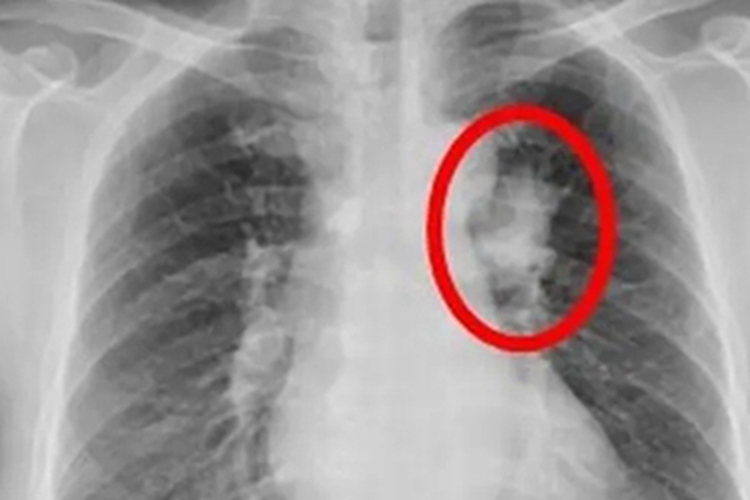

肺癌:肺癌患者会出现咳嗽、痰中带血、咳血、胸痛、胸闷气急、声音嘶哑等局部症状,以及发热、消瘦、贫血等全身症状。